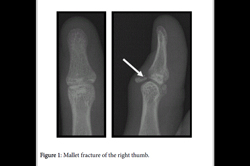

Mallet Finger